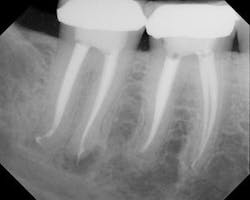

As a starting place, a discussion of how many and what type of digital pictures should be taken in advance of treatment is worth noting. Ideally, the clinician would want to take at least 2 films from different angles and more ideally 3 angles, mesial, distal and straight on from the buccal. Taking such multiple images from different angles with digital radiography is most ideal for ease of capture, timesaving and ability to interpret the various images using software. DEXIS is the chosen imaging system of the author (DEXIS digital radiography, Alpharetta, GA, USA). Patients will appreciate the reduced radiation and the lack of developing chemicals being used.

The author utilizes the K3 rotary nickel titanium (RNT) system and the elements obturation unit to deliver a RealSeal bonded obturation (SybronEndo, Orange, Calif.) with the SystemB obturation technique. The goal of these materials and technique is the 3-D cleansing, shaping and obturation of the canal space from the orifice to the apical foramen. In the empirical opinion of the author, these materials and technique choices are the state-of-the-art choices for endodontic treatment at the present time. See Figures 1 through 4.

Irrespective of the particular instruments used, to the greatest extent possible the goal is to achieve for the patient the net effect of extracting the tooth. Extraction works because the diseased pulp is removed and as such the patient heals. If the pulp space is properly cleansed and shaped the patient can heal because the irritated, inflamed or dead (in all cases, pathologic pulp) has been removed. See Figure 4.